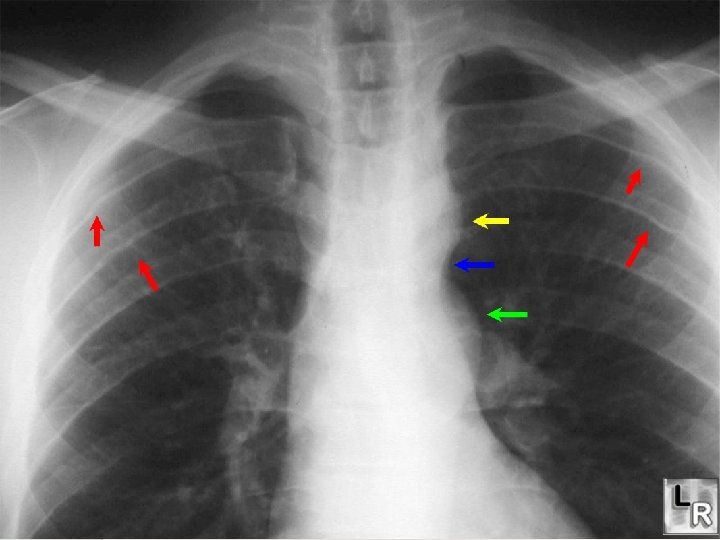

Transposition – Diagnosis and Treatment • Diagnosis • Chest X-Ray: “Egg on a String” • Echocardiography • Cardiac Catheterization (? ) • Treatment • Balloon septostomy during cardiac cath. • Rashkind’s Procedure • Reestablish Foramen Ovale • Prostaglandin E 1 to keep PDA open. • Surgical Correction • Jantene Operation

Coarctation – Diagnosis and Treatment • Diagnosis • Chest X-Ray • Echocardiography • Cardiac catheterization • Treatment • Support with inotropic agents (Dopamine). • Prostaglandins to maintain PDA. • Surgical repair